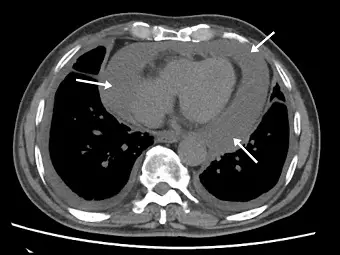

有心衰竭症狀的男性患者,未施打顯影劑的胸腔電腦斷層顯示心臟旁有不明病灶(如下圖箭號處)。經測量其密度約為 10 HU ,最有可能的診斷為何?

附圖為一張未施打顯影劑的胸部軸切面電腦斷層(Axial non-contrast chest CT)影像。

- 影像特徵:箭號所指處可見心肌外圍環繞著一圈均勻的低密度(low-attenuation)物質,該病灶局限於心包膜腔(pericardial sac)內,呈現新月形或環狀分佈。

- 密度比較:目視該病灶的灰階密度介於兩側肺野的空氣(極黑)與皮下脂肪(深灰)之上,但略低於中間的心肌與周圍的軟組織(淺灰)。此視覺特徵與題目所提供之測量數值「約 10 HU」完全吻合,確認為液體密度(fluid attenuation)。